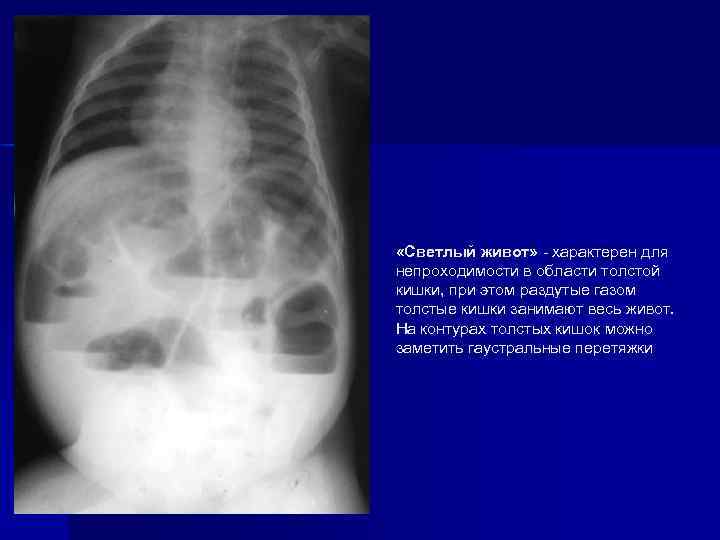

«Светлый живот» - характерен для непроходимости в области толстой кишки, при этом раздутые газом толстые кишки занимают весь живот. На контурах толстых кишок можно заметить гаустральные перетяжки